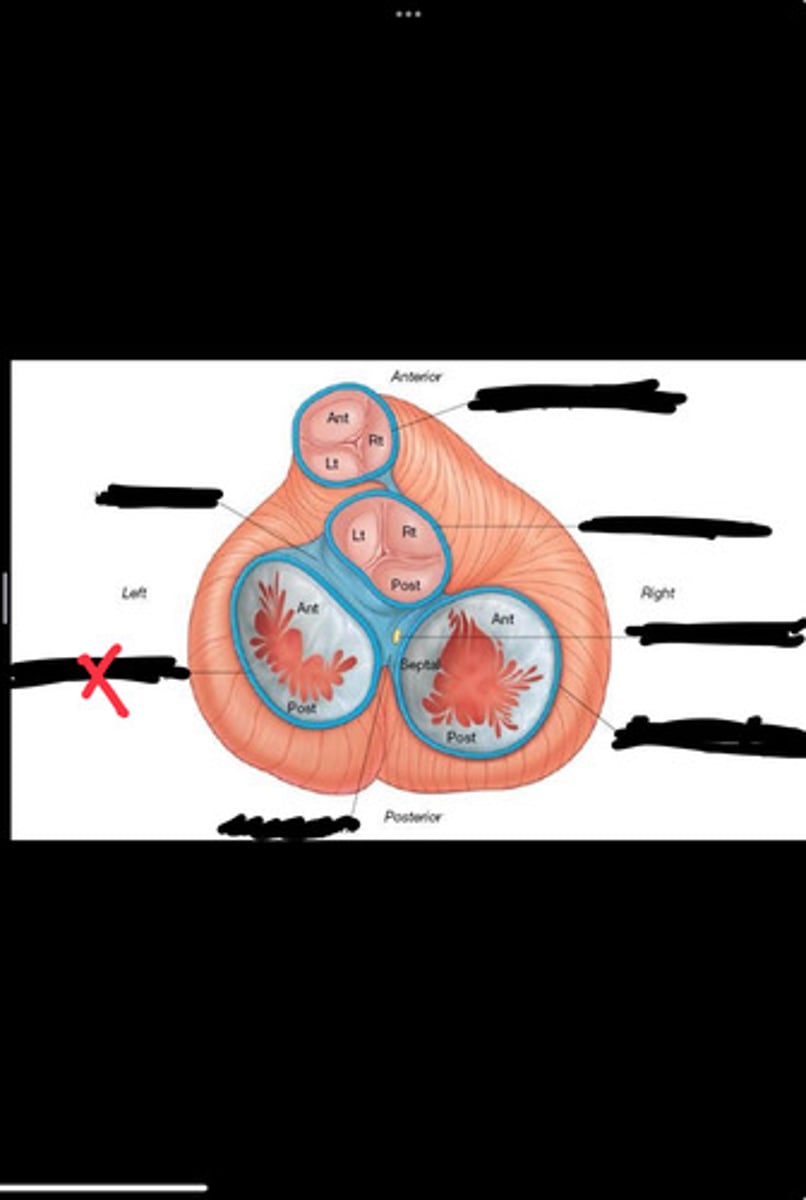

Right fibrous trigone

Left fibrous trigone

Fibrous ring of pulmonary valve

Fibrous ring of aortic valve

Atrioventricular bundle

Right atrioventricular ring

Left atrioventricular ring